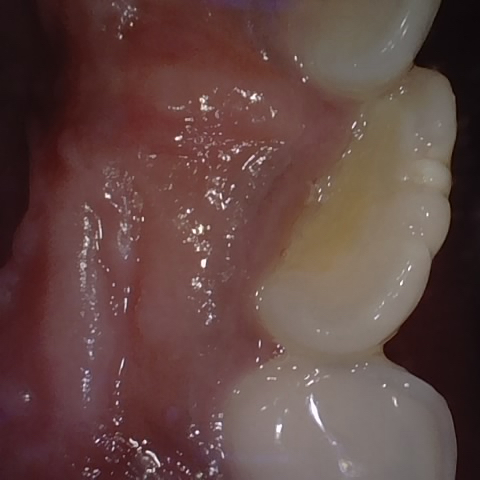

Incorrect Quality Level

The reference annotation for this image is

None

.

Please select the correct quality level.

Annotated as "Good"